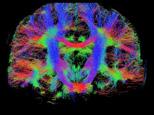

Finger tapping task: activation of Functional MRI a) Diffusion MRI and fiber tracking Post-mortem a) a) b) Fig 7 In a), an structural MPRAGE image acquired at 0 75mm isotropic (skull removed using FSL package) In b), fiber tracking based on DTI acquisition, 64 directions, 1 5mm isotropic resolution The colors are defined for different orientations of the fibers Fig 8: In a), susceptibility weighted images acquired at 0 35mm isotropic, 32 min acquisition time, in a post-mortem brain fixated with formalin In b), a photograph of similar slice in the same brain Table 1: 7T MRI studies conducted at the RF Research Facility at University of Pittsburgh White matter legions (circle): Multiple Sclerosis study Stroke (circle): sickle cell disease study Automatic hippocampus segmentation: Midlife Neurocognitive Lacunar infarct (arrow): depression study White matter hyperintensities (arrows): Healthy Brain aging study (left) and Small Vessels disease in preclinical Alzheimer’s disease study (right) Fig 9: Sample of some studies listed in Table 1 using the developed 16 array (Fig a) There are 4 completed studies and 13 ongoing patient studies with approximated 2 000 patients scheduled FUTURE DIRECTIONS 64-channel Tic-Tac-Toe RF transmit coil for 7T MRI 0 Fig 10: In a), the 64-channel transmit coil computational modeling [2] To improve the field of view of the projector/monitor in fMRI studies, the frontal panels can be removed, resulting in a 56-channel coil In b), one assembled side of the coil In c), simulated B1+ field distribution: for an 8kW power amplifier capabilities (default in older 7T MRI scanners) a homogeneity (measured by the coefficient of variationCV) of 15 2% is achieved in the brain For an 16 kW power amplifier (available for the recently FDA approved Siemens 7T MAGNETOM Terra), an CV of 10 6% can be achieved in the brain 16 kW power amplifier: 8 kW power amplifier: a) b) c) max